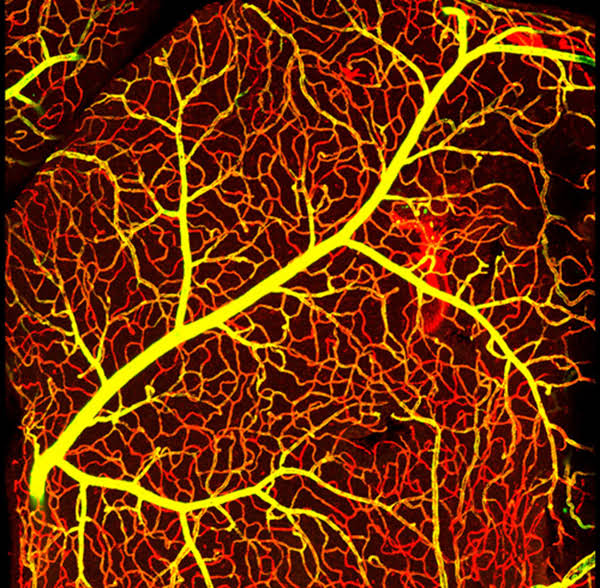

為促進科學(xué)文化發(fā)展,活躍專委會的科技人文氛圍,培養(yǎng)科研工作者的創(chuàng)新意識,激發(fā)他們發(fā)現(xiàn)美、創(chuàng)造美的熱情和興趣,本次年會特別增加了一項“生命的藝術(shù)——首屆年度顯微圖片展”活動。在專委會發(fā)出征稿通知之后,來自全國近20 所院校的師生積極響應(yīng),共投稿顯微攝影作品125 幅。經(jīng)以王松靈院士為主席的九位審讀專家組成員在線上線下的認真審閱和討論,從圖片的原創(chuàng)性、科學(xué)性和藝術(shù)性三個方面進行綜合考量,最終確定年度圖片1 幅,年度提名圖片20 幅。在此匯集成冊,與各位同仁分享、交流。

這些作品幾乎均為創(chuàng)作者在日??蒲泄ぷ髦幸圆煌募夹g(shù)手段捕捉到的微觀生命瞬間,科學(xué)的“透鏡”似乎為我們展現(xiàn)出一幅幅藝術(shù)的“魔幻”,一邊是細胞、分子層面的微觀抵達,另一邊好似一塊既陌生又熟悉的“優(yōu)詩美地”。這里,本是科學(xué)嚴謹?shù)念I(lǐng)地,因為其關(guān)乎生靈,便開啟人們自由逸放的審美思緒。在此,我們驚嘆中國古代哲學(xué)體系中“天人合一、道法自然”的天道規(guī)律。原來早于現(xiàn)代科學(xué),這種“盡精微而致廣大”的宇宙觀便已根植于我們生存的大地。感謝各位作者以他們現(xiàn)代技術(shù)的視野,為我們定格生命律動的瞬間,張揚蓬勃的藝術(shù)活力。換一個視角,生命的風景便呈現(xiàn)“天地人”的和諧和統(tǒng)一,換一種思路,生命的哲學(xué)便更能詮釋苦難與幸福的非凡境遇。